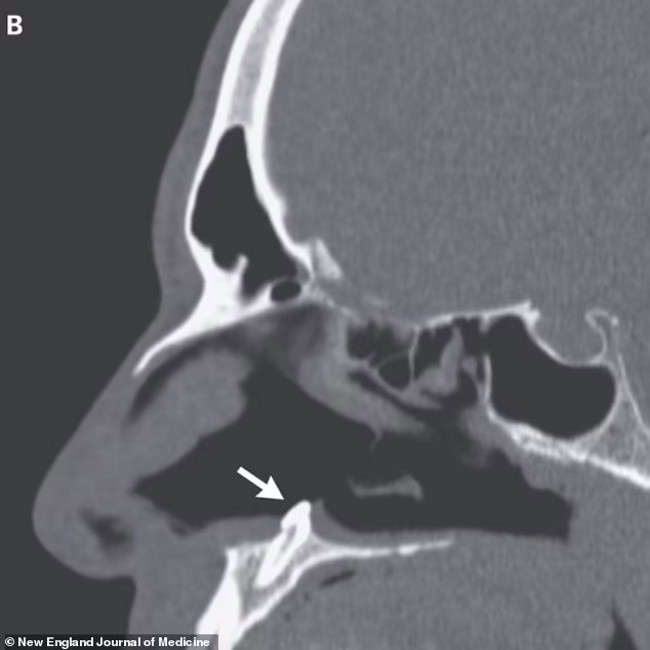

Врачи провели мужчине риноскопию и нашли в одной из ноздрей плотную белую массу, которая не вызывала болевых ощущений. Оказалось, что это эктопический зуб длиной 14 миллиметров, который вырос не там, где ему следовало бы.

Мужчине провели операцию и удалили зуб, вскоре проблемы с дыханием прекратились.